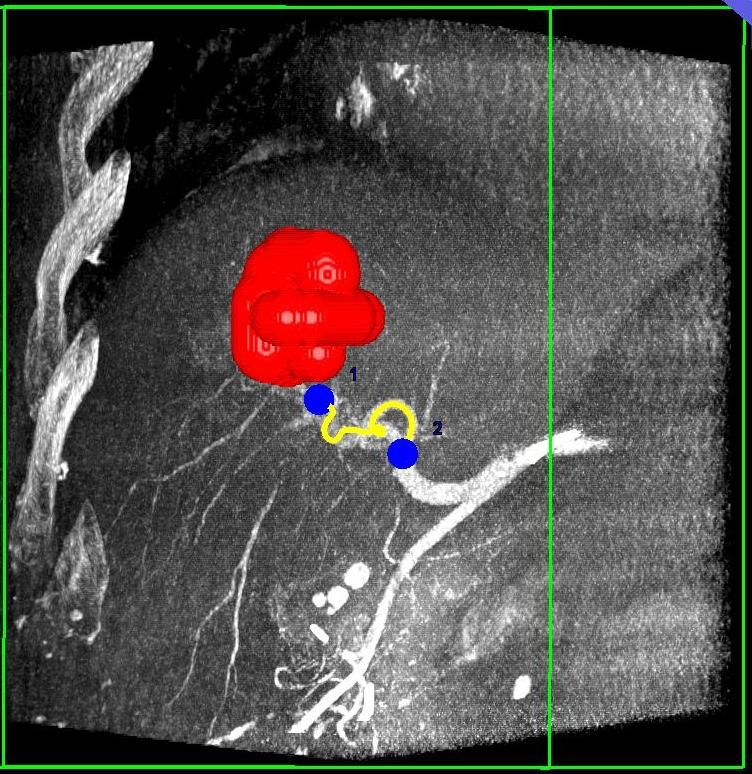

Präoperative Tumormarkierung

Eine Voraussetzung für die vollständige chirurgische Entfernung von Knochen- und Weichteiltumoren ist die präzise Erkennung der Tumorausdehnung und der Tumorgrenzen. Mit der Kernspintomographie (MRT) kann das Tumorgewebe exzellent von gesundem Gewebe abgegrenzt werden und somit die Ausdehnung vor der Operation bestimmt werden. Nach der kernspintomographischen Bestimmung der Tumorausdehnung werden unter kontinuierlicher MRT-Bildgebung die Grenzen des Tumors markiert. Die Marker werden mit einer Nadel ins angrenzende gesunde Gewebe eingebracht. Die Markierung kann am Tage vor der Operation durchgeführt werden. Alternativ ist die Tumormarkierung auch mit anderen bildgebenden Verfahren möglich, z.B. mit der Computertomographie oder dem Ultraschall.

Abbildung: Bei diesem Patienten wurde ein im Röntgen nur schlecht sichtbarer Knochentumor vor der Operation unter MRT-Kontrolle mit kleinen röntgendichten Spiralen („Coils“) markiert. Damit hat der Operateur eine optimale Darstellung des Tumorbereichs bzw. der Tumorgrenzen und kann gezielter, schonender und effektiver operieren.